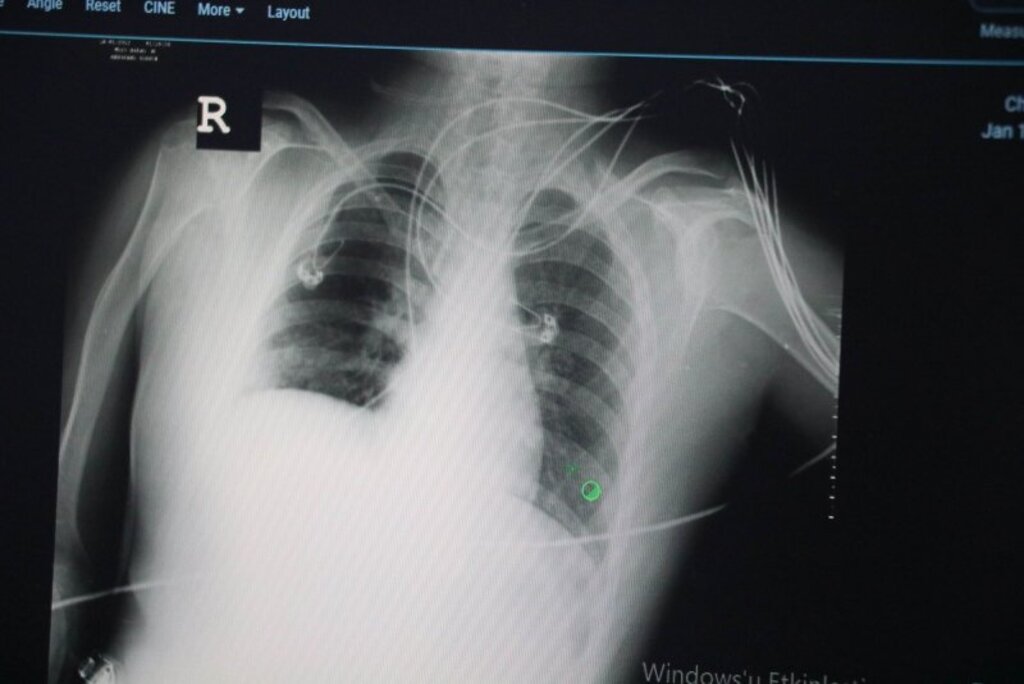

Kısa bir süre sonra pandeminin sona ermesini beklediklerini dile getiren Uzm. Dr. Nurullah Dikmen, "Şu anda gündemimiz Omicron varyantı. Daha önceden yaygın varyant, delta varyantıydı. Delta, Omicron'a göre daha hasta yapıcı özelliğe sahipti. Buna bir "Müjde" diyebiliriz. Omicron daha hızlı yayılıyor ama hastalandırma oranı oldukça düşük. Bunu 3-4 ay gibi bir sürede pandeminin biteceği müjdesi gibi algılıyoruz. Omicron'un en belirgin özellikleri, burun tıkanıklığı, boğaz ağrısı ve hapşırma. Öksürük, bu varyantta deltaya göre daha az görülüyor. Akciğer tutunumu, deltaya göre oldukça düşük. Belirli bir yaş ve alt hastalığı olanları tabi ki Omicron'da da hastalanabiliyor. Tat alma ve koku kaybının azalması Omicron'da daha az. Bunların dışında Omicron'da mide bulantısı, karın ağrısı, gece terlemesi ve bel ağrıları diğer varyantlara göre daha fazla oluyor. Omicron, klinik olarak diğer varyantlara göre daha iyi. Acile başvuru yüzdesi deltada yüzde 15’ken, Omicron'da bu oran yüzde 5’lere düştü. Hastaneye yatma riski deltada yüzde 4’te oranındayken Omicron'da ise yüzde 2’ye düştü. Hatta solunum cihazına bağlanma oranı da diğer varyantlara göre yüzde 80’e kadar düşüş var. Yani evde, ayakta geçirilen bir varyant hastalığını görüyoruz. Bulaşıcılığı fazla ama hastalandırıcı özelliği diğer varyantlara göre oldukça az” dedi.